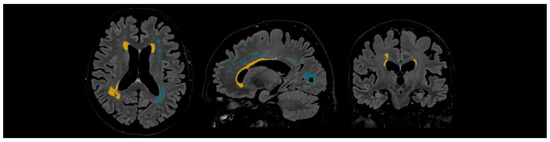

PVWMH Grade 1 was assigned to patients with mild hyperintensities that were found along the ventricular horns, also known as pencil-thin lining or “caps.” Grade 2 was assigned to patients exhibiting more hyperintensities, and Grade 3 was assigned to patients with lesions that extended into DWM (see Figure 1).

Figure 1. Periventricular white matter hyperintensities based on the Fazekas scale, ranging from Grade 1 to Grade 3, based on the severity of lesions.